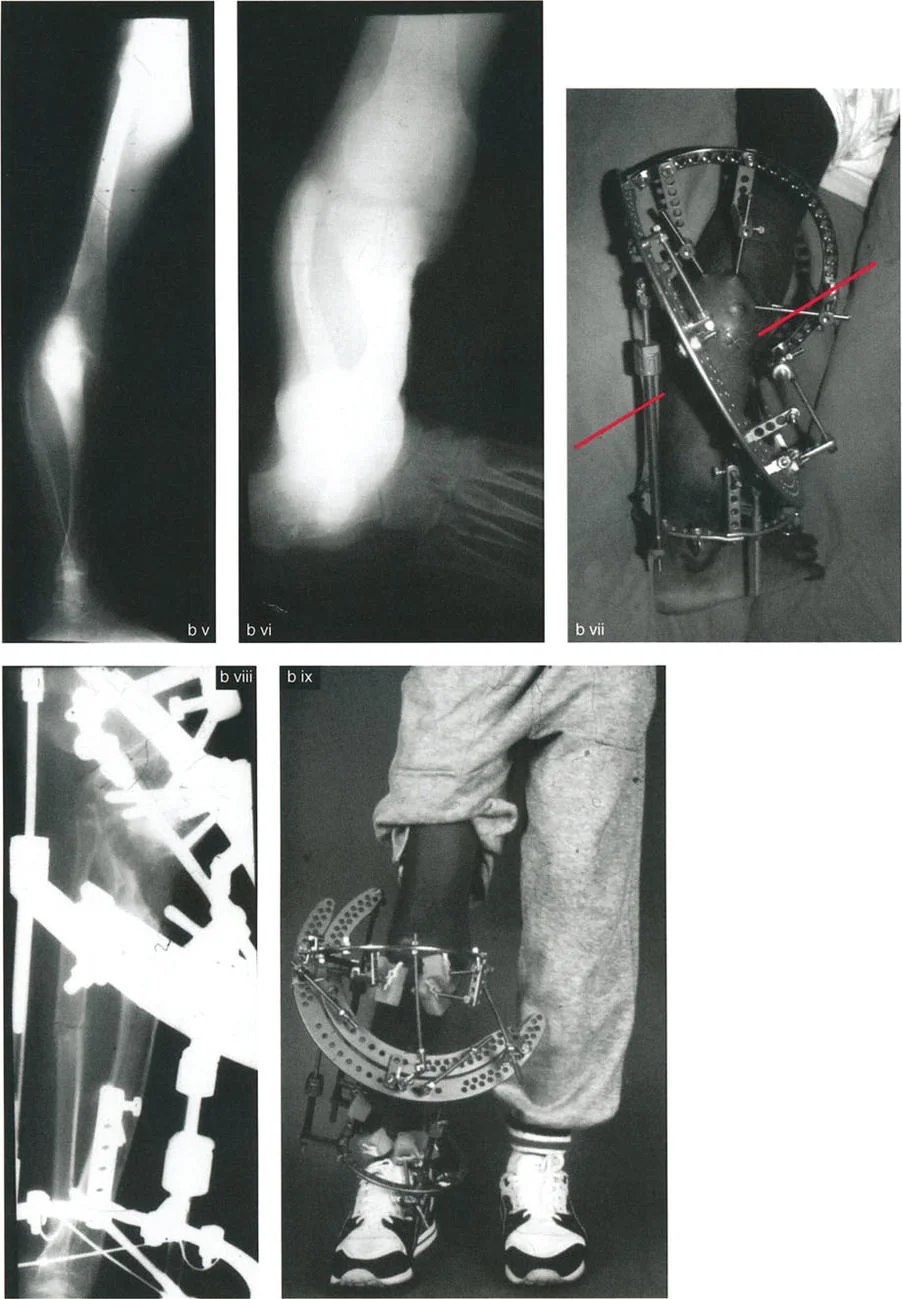

بالإضافة إلى الأشعة السينية المتخصصة، قد يطلب الأستاذ الدكتور محمد هطيف صوراً مقطعية (CT Scans) أو رنيناً مغناطيسياً (MRI) للحصول على رؤية ثلاثية الأبعاد أكثر تفصيلاً للعظام والأنسجة الرخوة والأعصاب، خاصة في الحالات المعقدة أو عند التخطيط الجراحي الدقيق.

تحديد مستوى التشوه بدقة

إن تحديد المستوى الدقيق للتشوه الدوراني هو أحد أهم الخطوات في التخطيط الجراحي. على الرغم من أن الدوران هو تشوه زاوي في المستوى المستعرض، إلا أن موقعه على طول العظم (قريب من المفصل أو بعيد عنه) يؤثر بشكل كبير على كيفية تصحيحه وتأثيره على الأنسجة المحيطة.

- في حالات ما بعد الإصابة: يكون مستوى التشوه واضحاً عادة عند موقع الكسر الملتئم.

- في الحالات الخلقية أو التنموية: يتطلب تحديد مستوى التشوه استنتاجاً سريرياً دقيقاً يعتمد على تأثيره العميق على مسار العضلات والأوتار. يعتمد الدكتور هطيف على خبرته الواسعة في تقييم هذه الحالات لتحديد المستوى الأمثل لقطع العظم.

هذه الدقة في التشخيص هي ما يميز نهج الأستاذ الدكتور محمد هطيف، وتضمن أن خطة العلاج ستكون مصممة خصيصاً لحالة المريض، مما يقلل من المخاطر ويزيد من فرص النجاح.

خيارات العلاج المتقدمة لتصحيح التشوهات الدورانية

عندما تكون تشوهات الدوران والانحراف الزاوي شديدة وتؤثر على وظيفة المريض أو تسبب ألماً مزمناً، يصبح التدخل الجراحي هو الحل الأكثر فعالية. تتطلب هذه الجراحات دقة متناهية وتخطيطاً متقدماً، وهو ما يبرع فيه الأستاذ الدكتور محمد هطيف